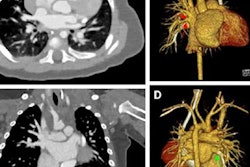

PCCT produces images without electronic noise, improved tissue characterization, and optimized spectral imaging while using less iodine and radiation.

Dr. Marc Kachelriess of the German Cancer Research Center in Heidelberg expanded on the pros of PCCT, describing how the lack of electronic noise translates to a lower radiation dose, particularly for infants, and less noise for studies of obese patients. Additionally, Kachelriess listed other benefits, including how PCCT offers an improved iodine contrast-to-noise ratio, as well as spectral information on demand, and how its smaller pixels lead to higher spatial resolution.